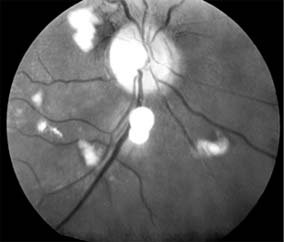

Systemic lupus erythematosus, associated with the presence of circulating antibodies to DNA, produces an occlusive vasculitis of the nerve fiber layer of the retina. Such infarcts result in retinal cotton-wool spots (Figure 16-7).

Figure 16-7

Figure 16-7: Cotton-wool spots in the retina of a patient with systemic lupus erythematosus.